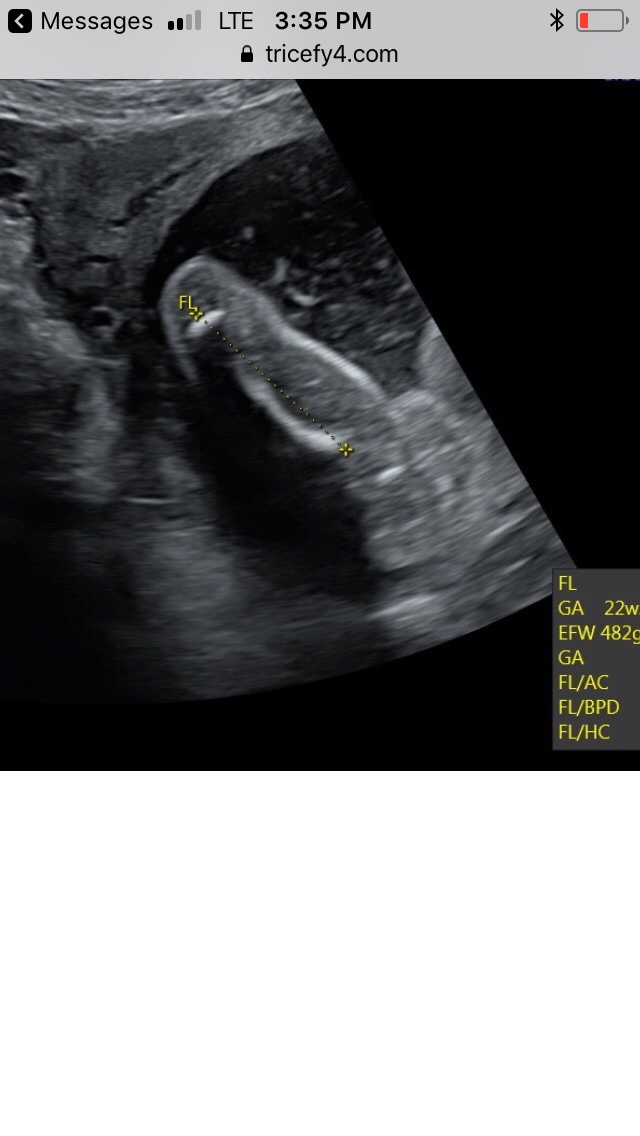

At my 21 week scan, we did not find out the gender, but I kind of want to guess based on the shots I got. Tell me what you think based on this pic when the tech measured the thigh...Attachment 41162

im not the best at tricky pics but if im looking at this right then id lean towards girl.. im looking at it as the thigh on the left being measured then what i think is baby's other thigh cut off on the right of the pic so im looking between those 2 things.. i could be looking in completely the wrong place though!!

It looks girly to me - but the techs see way more than us in the scans.